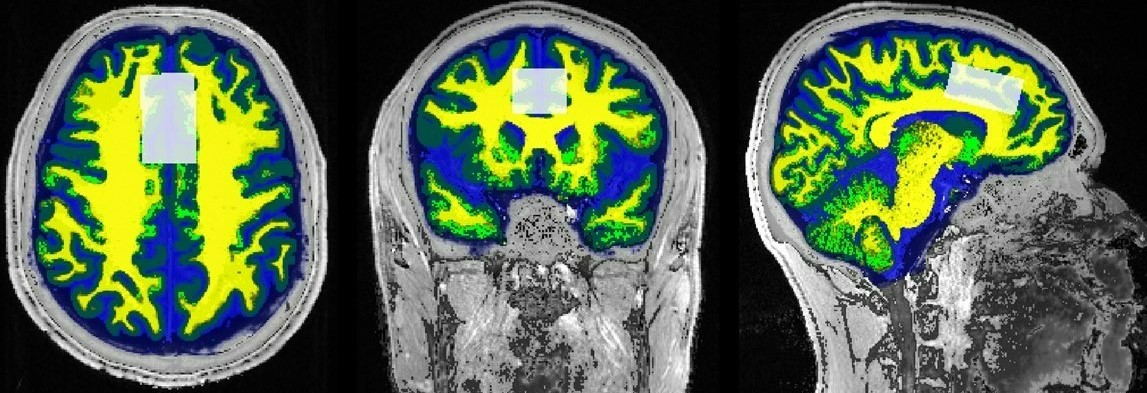

A total of 7 offenders over the age of 18 were treated with Sertraline (Setrona) and selected to participate in this sub-study. All MRI/MRS scans were undertaken on a 3T (Prisma, Siemens) MRI scanner equipped with a 64-channel coil. MRI/MRS data was acquired from the offender cohort at 2 timepoints; baseline (BL, i.e. before commencement of Sertraline) and 3-4 weeks follow-up (FU) of the SSRI intervention. Structural imaging using 3D T1-MPRAGE (TR/TE/TI=2000/3.5/1100ms, FOV=256x256mm2, voxel size:1mm3) as well as 3D T2-FLAIR (TR/TE/TI=5000/386/1800ms, FOV=256x256 mm2, voxel size: 1mm3) were acquired. H-MRS was applied using a Point RESolved Spectroscopy (PRESS) sequence acquired from the anterior cingulate cortex (ACC) (Figure 1) with the following acquisition parameters: TR/TE=2000/30ms, ACC voxel size =40x25x20 mm3, averages=128 with water suppression. Lastly, the parameters used for the MEscher-Garwood PRESS (MEGA-PRESS)8,9 scans were as follows, TR/TE=2000/68 ms, bandwidth=1200Hz, averages=128. FSL and SPM12 were used for total brain volume, grey matter (GM), white matter (WM), CSF volumes and segmentation of the MRS voxels10,11 (Figure 1). MRS data was exported offline and underwent post-processing using two methods, Gannet (analysis of GABA and Glx concentrations) and LCModel (analysis of major metabolites). Volumetric measures and the level of significant change in metabolite levels over 4 weeks were assessed using repeated measures ANOVA, with age and sex as covariates, followed by post hoc testing using Bonferroni.

Figure 1 - T1-weighted MR images in axial, coronal and sagittal planes, depicting the ACC voxel size, position (white box), and tissue segmentation (WM-yellow, GM-green and CSF-blue).